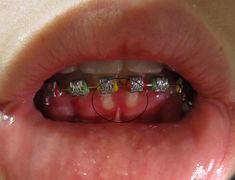

Mouth

Mouth images